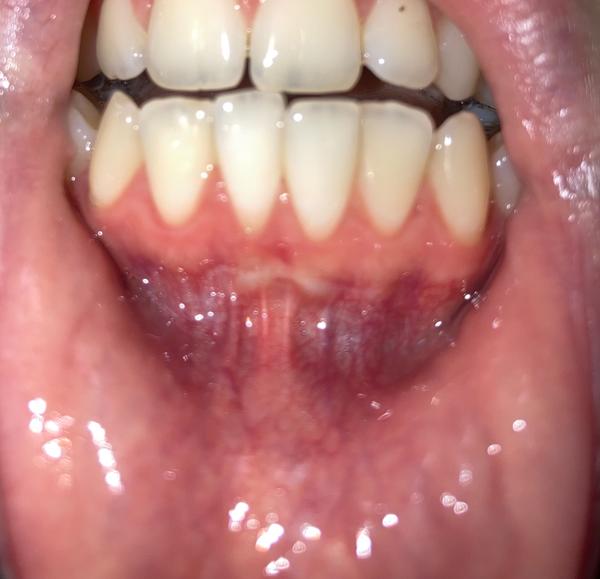

chcela by som sa poradiť ohľadom môjho problému. Pred pár rokmi som bola na odstránenie uzdičky.

Je ružová farba z tohto zákroku?

Mám zápal ďasien?

Nemám bolesti a ani krvácanie.

myslím si, že nemáte zápal ďasien. Ak by išlo o zápal ďasien, tak by sa to prejavilo ako paradontóza, ďasná by krvácali.